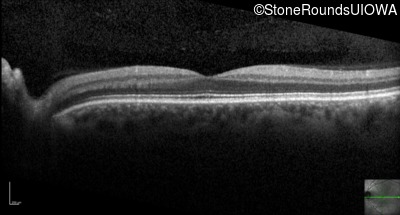

Optical Coherence Tomography - Left - Count Fingers 4' sc

Exemplar / OCT Stack